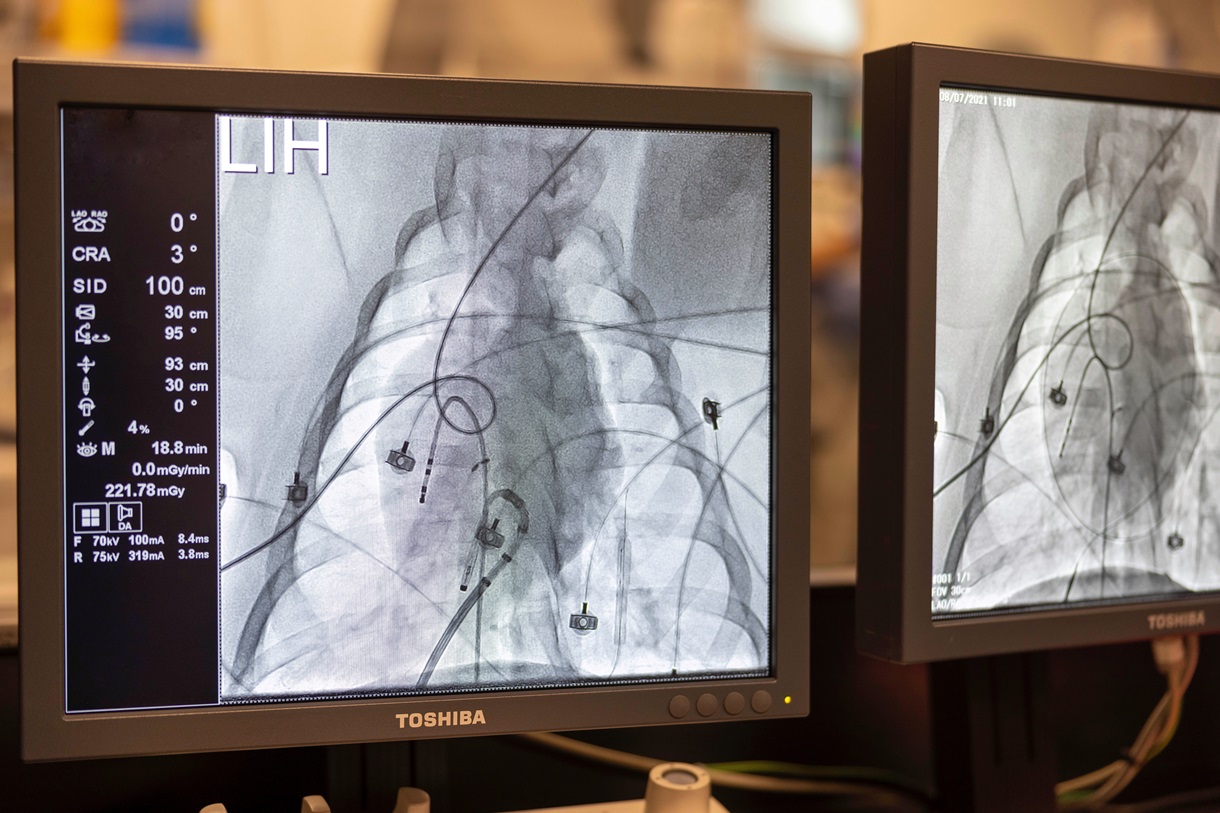

CMCiB has an extensive track-record in the validation of medical devices in large animal models, offering services for proof-of-concept or functional studies, either acute or chronic, for implants, surgical sutures, stents, muscular electrostimulation devices, endovascular devices or techniques such as Transcatheter Aortic Valve Implantation (TAVI) procedures for research institutions and medtech companies worldwide.

With this regulatory milestone, the CMCiB consolidates itself as one of the few national public research centres with GLP certification specialised in the validation of medical devices (registration code BPL059CAT) and strictly adheres to international research standards for preclinical studies. The animal care and welfare program, professional training, documentation of the studies conducted, and the facilities and equipment of the advanced surgical area, as well as the animal housing facilities, have been inspected for the renewal of its certification. These spaces and equipment include highly equipped operating rooms, and imaging technologies such as ultrasound, magnetic resonance imaging, and interventional vascular radiology.

Since the centre's inception, the advanced surgery team has been involved in development and functional validation projects for a wide range of medical devices in various therapeutic areas and for different indications, such as prostheses, catheters, valves, stents, embolizing fluids, biodegradable implants, etc., which have been fundamental in achieving the experience and establishing the quality and demanding system required for GLP certification. During the first accreditation period, the centre marked a significant advance by incorporating its first GLP studies for medtech clients.

The company iVascular, founded in 2010 in Barcelona with the aim of developing medical devices and therapies for the treatment of vascular system disorders, has been a key client in the development of the first GLP studies at CMCiB, contributing to building a portfolio of projects and a trajectory of multiple safety, efficacy, and technical viability studies in a porcine model with some of its embolizing products. In its pipeline, iVascular has a wide range of coronary, peripheral, and neurointerventional products with solid scientific evidence within its iVasTriam clinical trials program, demonstrating the efficacy and safety of the products.